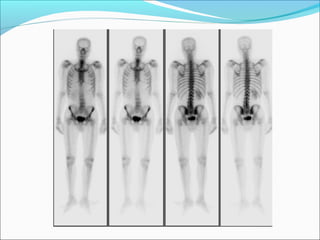

CRF

DTPADTPA

GFR = 25 ml/’

Creat = 3.0

L= 33%

R= 67%